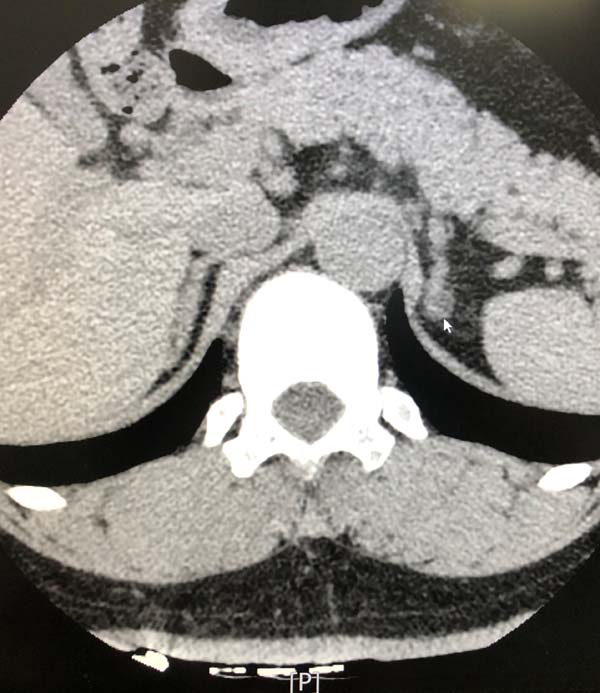

49岁的郭先生因“发现血压升高3个月,头晕1周”就诊于医院心内科门诊。高血压专科团队的主治医师高蕾接诊后考虑患者很可能是继发性高血压,就为患者调整了降压药物,将影响进行高血压激素检测结果的降压药物停用,换为无影响的特拉唑嗪。患者经过严格的药物洗脱2周后,收入心内科病房进行了规范的肾素醛固酮卧立位试验及卡托普利确证试验以及肾上腺的增强CT检查。结果发现患者双侧肾上腺结节,卧立位和确证试验结果都是阳性,原发性醛固酮增多症诊断成立,应进一步行双侧肾上腺静脉取血术(AVS),以确定优势侧,指导下一步手术治疗。

心内科的高血压专科团队立刻急性紧张的术前准备,制定围术期管理流程,梳理术中操作细节,准备手术耗材。8月11日上午,医院高血压专科团队在三楼导管室,成功施行了医院首例双侧肾上腺静脉采血术(AVS)。患者取平卧位在清醒状态下,经局麻穿刺右肘正中静脉,在X线透视指引下,选用特制导管成功在双侧肾上腺静脉、下腔静脉进行6部位取血送检。最终精准确定左侧肾上腺为分泌优势侧。术后患者经局部压迫止血后即可正常活动,与患者再次沟通,患者同意行左侧肾上腺切除手术。